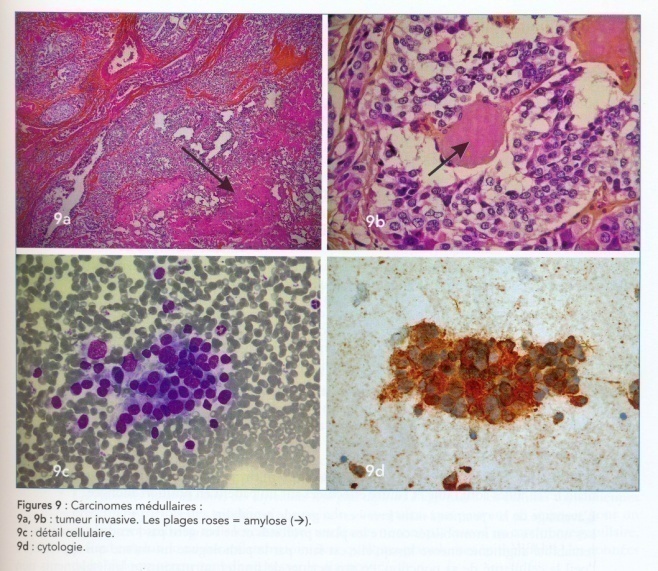

Фотографии опухоли медуллярной аденокарциномы

Раздел: Снимки-откровения